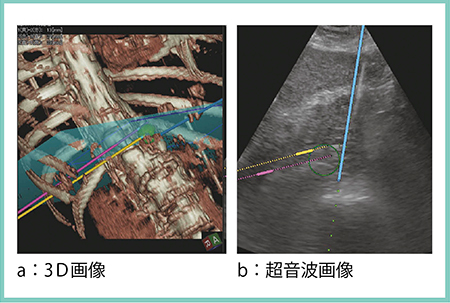

マルチポーラRFAのうち,腫瘍を直接穿刺せずに焼灼を行うNo-touch ablationには特に効力を発揮している。症例2では,3D Sim-Navigatorの3D画像(図5)にて,3本の電極針(▶)が腫瘍(←)をしっかりと囲んでいることが確認できる。

図5 症例2:No-touch ablation